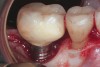

Fig 2. The height of this abutment was less than 2 mm on the facial. This may have led to additional marginal bone loss. Bacterial colonization of the abutment and the exposed implant body resulted in peri-implantitis.

Figure 2